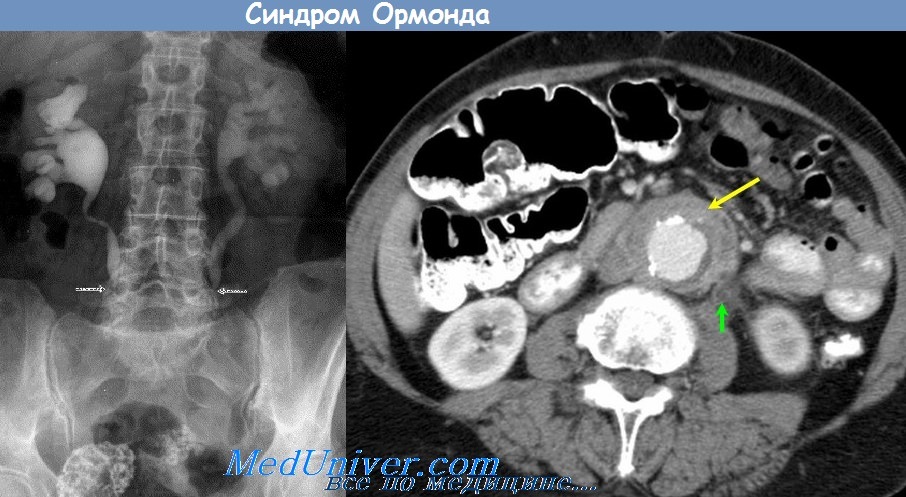

КТ ретроперитонеального фиброза: Изображения и диагностика